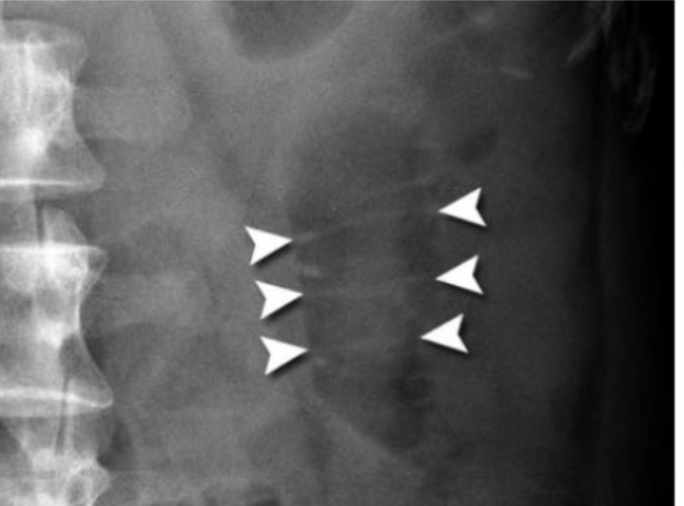

What is this and what type of scan

Calcifications, AXR